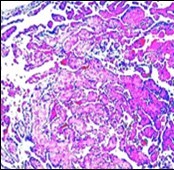

On microscopy, superficial squamous epithelial surface is intact. Sub-epithelial connective tissue stroma exhibits slit-like, vascular spaces. Upon extended magnification, multiple, intravascular papillary projections encompassed within a hyalinised stroma are discerned. Centroidal calcification appears in combination with intravascular, papillary endothelial cell proliferation, lined with singular layer of endothelial cells devoid of cytological atypia6, 7.

Characteristically, the vascular neoplasm denominates numerous papillae within blood vessels. Papillae are coated with singular or dual layer of flattened endothelial cells with an encompassing hyalinised, fibrous tissue core. Vascular lumen is distended with thrombosis. Foci of haemorrhage with fibrinous and purulent exudate are discerned. Tumour perimeter depicts inflammatory granulation tissue. Cholesterol clefts and focal reactive bone formation may concur. Extraneous squamous epithelium may be discontinuous and ulcerated. The neoplasm is devoid of features of malignancy4, 6.

Numerous micro-calcifications can be observed within the lesion which may engender vascular occlusion and tissue necrosis6. Figure 1, Figure 2, Figure 3, Figure 4, Figure 5, Figure 6, Figure 7, Figure 8.

Figure 4.Papillary endothelial hyperplasia enunciating papillary arrangements coated with single layer of endothelial cells intermingled with significant fibrinous and thrombotic exudate13.